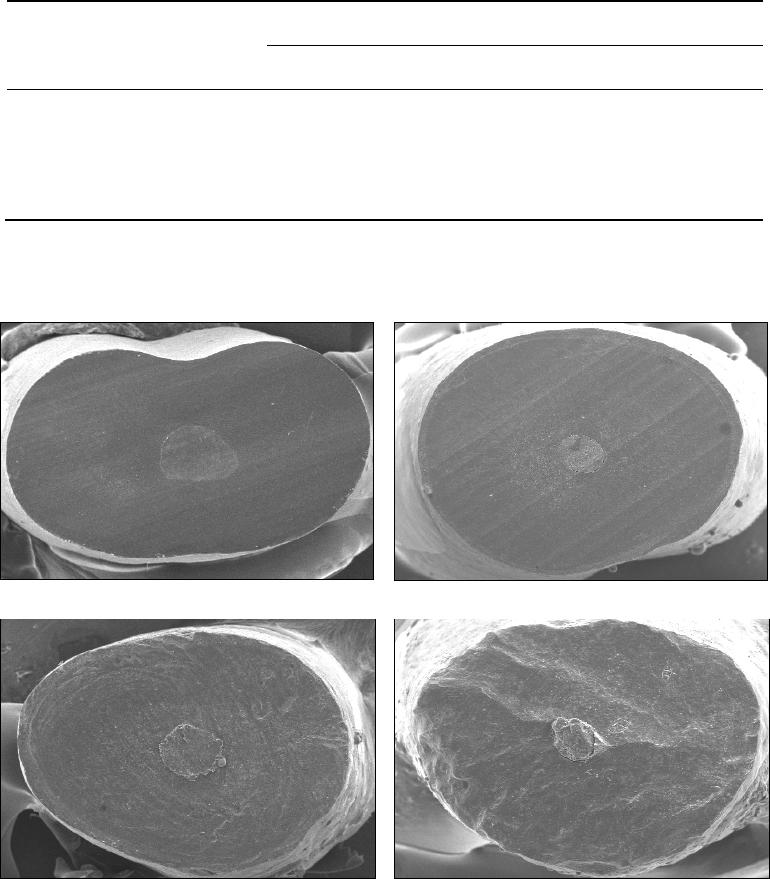

A qualidade da superfície radicular foi analisada de acordo com os seguintes

escores adaptado de Morgan, Marshall

24

(1998): 1 – superfície essencialmente de

aspecto vítreo, sem a presença de marcas de instrumento; 2 – superfície

essencialmente lisa, mas com discretas marcas de instrumento; 3 – superfície

visivelmente estriada, revelando nítidas marcas de instrumento; e 4 – superfície

irregular, com marcas grosseiras de instrumento de profundidade exagerada (Figura

1).